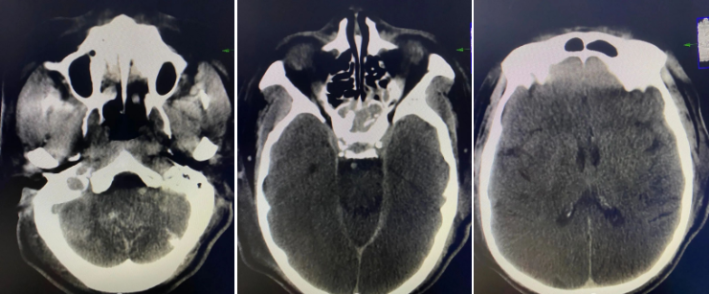

术后CT未见出血,期待良好预后。